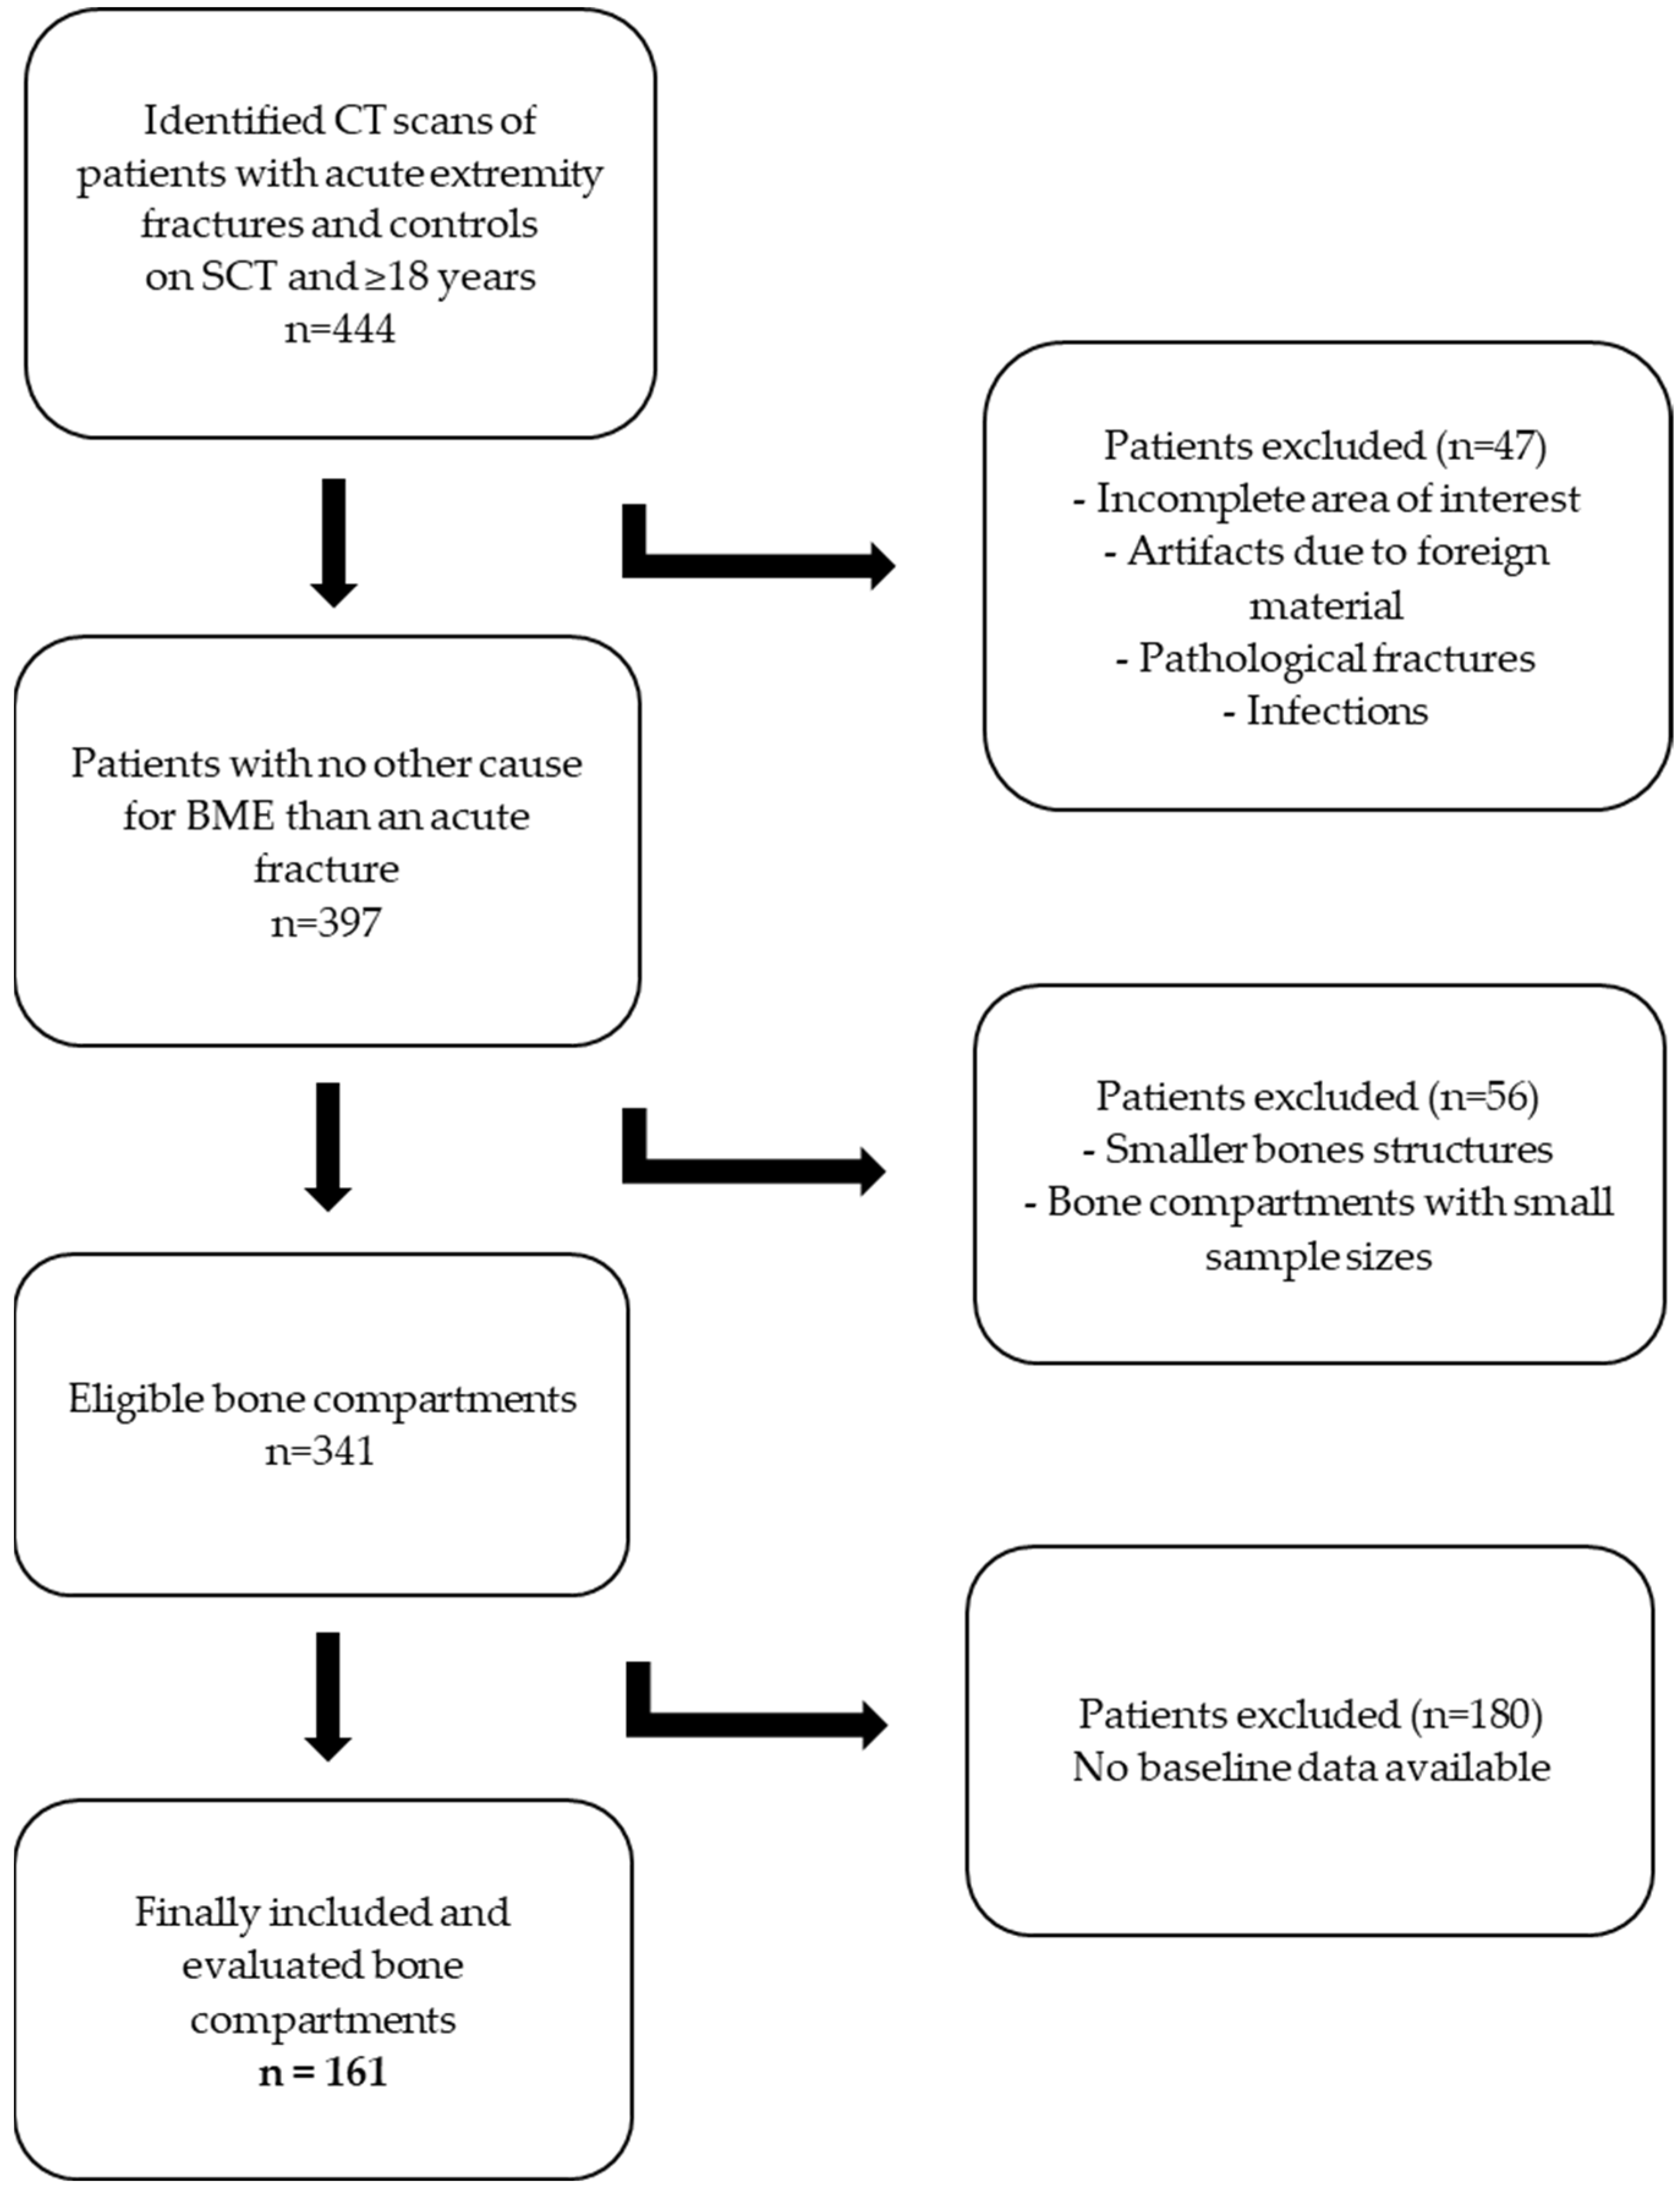

2. Materials and Methods

3.1. Baseline Data